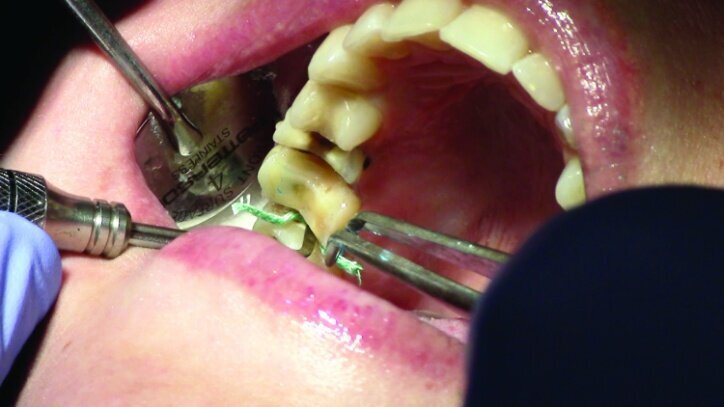

Tissue management was obtained with ViscoStat Clear, gingival haemostatic gel, 25 percent (m/m) aluminum chloride (Figs. 16 & 17). Gingival retraction was obtained using a two-cord system. First, a #00 size cord from Ultradent was placed on the mesial and distal of both preparations (Figs. 18 & 19).

Additional haemostatic gel was used prior to the second cord. The second cord was #2 size cord from Ultradent (Figs. 20 & 21a). A minimum of four minutes with both cords in place is needed for adequate retraction of the soft tissue (Fig. 21b).